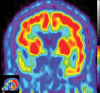

Neurodegenerative diseases are a devastating group of disorders that can be difficult to accurately diagnose. Although these disorders are difficult to manage owing to relatively limited treatment options, an early and correct diagnosis can help with managing symptoms and coping with the later stages of these disease processes. Both anatomic structural imaging and physiologic molecular imaging have evolved to a state in which these neurodegenerative processes can be identified relatively early with high accuracy. To determine the underlying disease, the radiologist should understand the different distributions and pathophysiologic processes involved. High-spatial-resolution MRI allows detection of subtle morphologic changes, as well as potential complications and alternate diagnoses, while molecular imaging allows visualization of altered function or abnormal increased or decreased concentration of disease-specific markers. These methodologies are complementary. Appropriate workup and interpretation of diagnostic studies require an integrated, multimodality, multidisciplinary approach. This article reviews the protocols and findings at MRI and nuclear medicine imaging, including with the use of flurodeoxyglucose, amyloid tracers, and dopaminergic transporter imaging (ioflupane). The pathophysiology of some of the major neurodegenerative processes and their clinical presentations are also reviewed; this information is critical to understand how these imaging modalities work, and it aids in the integration of clinical data to help synthesize a final diagnosis. Radiologists and nuclear medicine physicians aiming to include the evaluation of neurodegenerative diseases in their practice should be aware of and familiar with the multiple imaging modalities available and how using these modalities is essential in the multidisciplinary management of patients with neurodegenerative diseases.©RSNA, 2020.